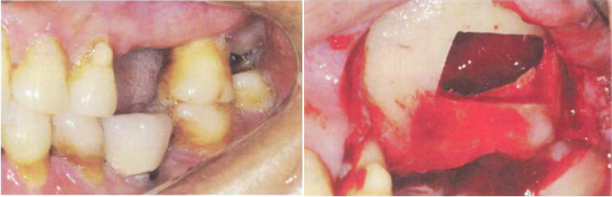

图 3 用骨刀进行切割手术的示意图

“一种植牙微创无痛手术用超声骨刀及使用方法”是童娟创新研发的其中一项技术专利,其核心产品--超声骨刀,具有诸多领先的技术优势。在切割操作方面,该超声骨刀搭载28-32kHz压电超声技术,利用高频振动产生的微小振幅,实现了对骨组织切割的精准操控。其切割误差可严格控制在≤0.1mm,远远超越了传统骨刀的精度水平。这项技术的独特之处还在于,其高频振动仅对骨组织产生作用,对血管、神经等软组织具有天然的“选择性”。在手术过程中,超声骨刀能够精准识别并分离骨组织,有效避免对周围脆弱软组织的牵拉和损伤。这种高精度的切割能力与组织识别特性,极大地提升了手术的安全性。医生在操作时无需担忧误伤重要组织,能够更加自信、从容地进行手术,显著降低手术风险。特别是在复杂植牙场景中,童娟的超声骨刀的精准切割优势发挥着关键作用。以上颌窦底提升手术患者为例,上颌窦底部与牙根、神经血管束等重要结构毗邻,传统骨刀操作时,一旦出现偏差,就可能损伤上颌窦黏膜导致穿孔,引发上颌窦炎等并发症,或损伤神经造成患者术后长期麻木不适。童娟研发的超声骨刀基于其精准识别和选择性切割特性,能够沿着骨-黏膜界面进行精细分离。在手术过程中,医生可利用超声骨刀将上颌窦底骨壁精确折断并提升,同时完整保留窦黏膜,如同“剥蛋壳”般精准,避免损伤周围重要结构,为后续植骨和种植体植入提供安全可靠的操作空间,显著提高手术成功率和患者术后生活质量。